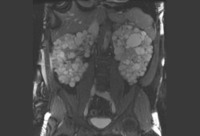

Ressonância nuclear magnética (RNM) do abdome e da pelve de paciente com doença renal policística sintomática

Da coleção do Dr. M. Hogan